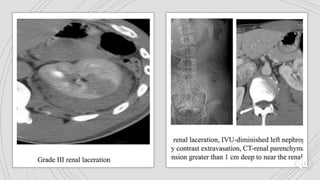

Grade I Grade II Grade III Grade IV Grade V

Are deeper lacerations

(>1cm) that do not result in

urine leak. Any injury

occurring in the presence

of a vascular injury

Grade I GradeII Grade III Grade IV Grade V Contusions and subcapsular hematoma are key terms used In the identification Perinephric hematomas & renal parenchymal lacerations are key terms Are deeper lacerations (>1cm) that do not result in urine leak. Any injury occurring in the presence of a vascular injury Include injuries to renal parenchyma and collecting system as well as vascular injuries. Shattered kidney, avulsion or laceration of the main renal artery , vein and devascularised kidney with active bleeding Contusions appear on portal venous phase CT images as globular, ovoid or round poorly demarcated area of relatively poor enhancement Hematomas contained within the gerota fascia has been postulated to have a tamponade effect on renal bleeding, resulting in perinephric clot formation Vascular injuries include pseudoaneurysm or arteriovenous fistula. Lacerations extending deep to involve the collecting system with urinary extravasation are included. Loss of identifiable renal parenchymal anatomy Hilar vascular injuries are not common. Subcapsular hematoma are confined by renal capsule. These are non enhancing cresentric or lentiform shaped fluid collections Lacerations are superficial (<1cm) and there is no urine leak These have been described as a focal collection of vascular contrast enhacement that shows decreasing attenuation with delayed imaging Delayed imaging usually shows urine leaking into the perirenal space Complete arterial tears result in retroperitoneal hematomas with possible active bleeding.